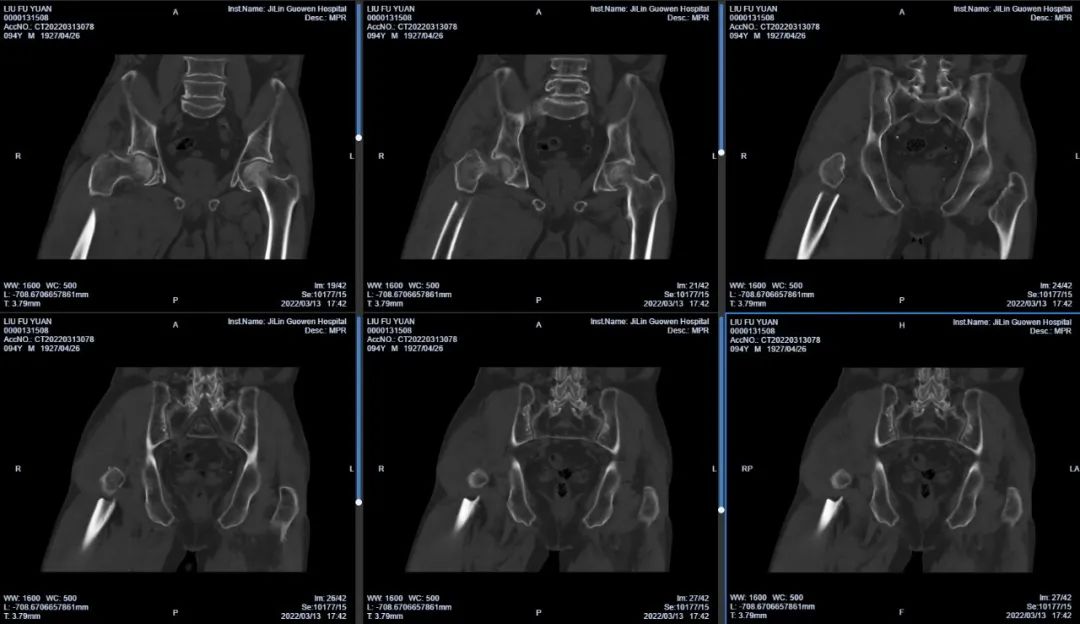

3月13日伴著急促的腳步聲、轆轆的車(chē)輪聲,夾雜著患者痛苦的呻吟聲,一位94歲的高齡老人被急診科醫(yī)護(hù)人員緊急送至骨科療區(qū)。這是怎么回事?呂國(guó)褔主任帶著值班醫(yī)生在做好防護(hù)措施后,第一時(shí)間來(lái)到患者病床前,經(jīng)急診科醫(yī)生診斷告知為 “股骨近端粉碎性骨折”,患者右大腿近端嚴(yán)重畸形,骨折端已經(jīng)刺穿前方肌肉直達(dá)皮下,局部皮膚高高隆起,局部皮膚有挫傷灶,呈青紫色,皮膚變薄,皮膚外可明顯觸及骨折斷端,右股骨X線(xiàn)片示:右股骨近端粉碎性骨折,斷端移位明顯,斷端銳利,近斷端位于前方皮膚下,局部皮膚隆起?;颊咛弁磩×?,痛苦難耐,測(cè)生命體征:血壓:220/110mmHg。